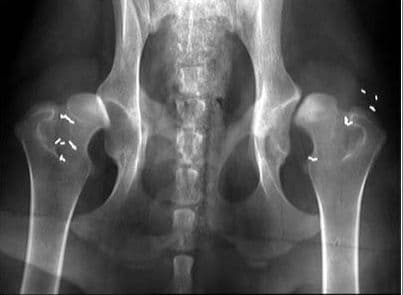

– Tràn dịch trong khớp, giãn rộng khe khớp, đường mỡ quanh khớp bị nén lại.

Những hiện tượng này có thể được phát hiện thông qua chụp X- quang. Đến nay, y học vẫn chưa xác định được rõ nguyên nhân gây bệnh.